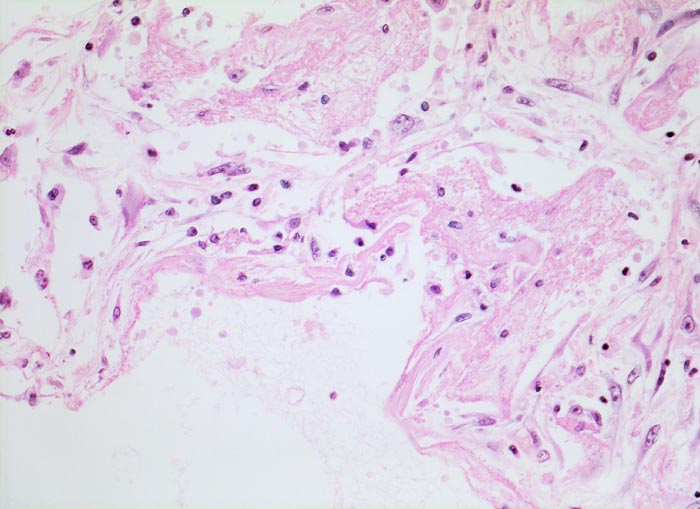

PathoPic – image database / PathoPic ID 4690 - Diffuser Alveolarschaden: hyaline Membranen

Diffuser Alveolarschaden: hyaline Membranen

Die Alveolarwand ist austapeziert mit einer homogenen, eosinophilen hyalinen Membran. Die hyaline Membran besteht aus fibrinreicher Ödemflüssigkeit gemischt mit Bestandteilen nekrotischer Epithelzellen. (= exsudatives Stadium der fibrosierenden Alveolitis). Die aufgelockerten Alveolarwände enthalten Fibroblasten und Makrophagen.

Bei der hyalinen Membranenkrankheit des Neugeborenen (IRDS) handelt es sich trotz morphologischer Ähnlichkeit mit den hyalinen Membranen der fibrosierenden Alveolitis um eine andere Erkrankung (mangelnde Surfactantbildung).